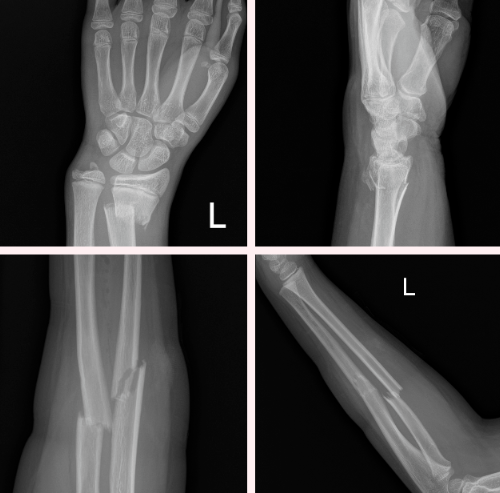

而且一旦發生了

輕則皮膚擦傷,重則骨折